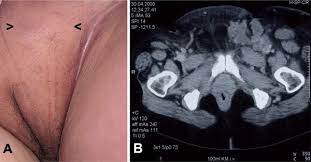

Suggested skin care tips, returning gradually to your usual skin care regime when your skin has returned to normal. I was first diagnosed with squamous cell carcinoma of the right groin lymph nodes with unknown primary in august, 2009. The whole area is still red, but instead of a rash, it looks like 2nd or 3rd degree burns to my entire groin area, with some areas still seeping, and others beginning to develop scabs, which i guess means i'm healing. An itchy crotch can be a bummer. Last week or so the ache is on both side in my groin and armpit areas. Patients having the condition generally experience reddened plaques, which are slightly raised skin patches, or crusted skin eruptions. A lump in this area of the body could be sign of condition. Does anyone have any experience to share with me please.

It's not a condition in itself but a. Yorkie maltese mix 3 years old. The rash has cleared up. I had cup in the left groin lymph nodes back in 2001. However, if conditions are right they can 'invade' Know what can cause pain in groin area. This is commonly seen together with obesity, resulting from diabetes type 2 or other conditions that affect the levels of insulin. Birth control pills can cause a woman to have dark groin skin. Hi i had radical surgery 17 days ago for squamous cell cancer in my groin. A swelling and/or lump in one or both of the testes; A feeling of heaviness in the scrotum; The cancer has spread to distant parts of the body (any t, any n, m1). The medical term for a blood clot is thrombus.

The groin is an uncommon place to get a skin cancer as it is not exposed to the sun as much as other parts of the body.

I also finished the ebrt mid february 2020. This is the only type of fat that is visible from the outside. Now his hind leg is sore and it seem swollen on 1 side in his groin area.? Nodes in the groin region (called the inguinal or femoral lymph nodes) may grow in size as a result of an injury or infection in your foot, leg, groin, or vagina. But scratching only makes the situation worse. Dark, thicker patches of skin: cancer and bumps that keep getting bigger; It was poorly differentiated, but had similarities to both squamous and small cell cancer, so i was treated with chemotherapies that worked for both of those types. Learn more about how to deal with. Patients having the condition generally experience reddened plaques, which are slightly raised skin patches, or crusted skin eruptions. A swelling and/or lump in one or both of the testes; groin pain and swelling could be red flags for males and potentially indicate many different conditions such as swollen lymph nodes in the male groin area or a hernia. I am healing well they tell me but i have dreadful nerve pain down the inside of my leg especially at night and walking is very difficult.

In order to do so a larger incision extending up toward the abdomen must be made skin cancer groin. It is usually caused by an unrelated underlying condition, like diabetes, cancer, or other disease or disorder.